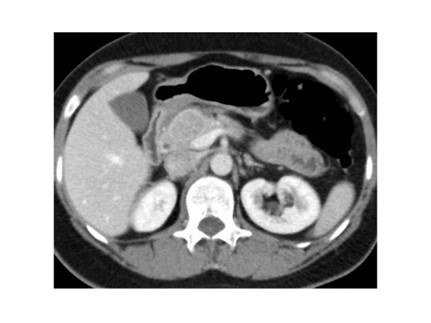

Tomografía de abdomen y pelvis con cte ev: del 13/10/2023.

Complicaciones posquirúrgicas

Ahora bien, como se mencionaba al principio, el estudio ecográfico es de muy baja sensibilidad y se identifique o no la lesión por este estudio, nuestro siguiente paso en el algoritmo diagnóstico de esta lesión es la tomografía. Esta es la prueba no invasiva inicial, con una sensibilidad del 63% al 83%, y detecta del 70% al 80% de los tumores. Esta debe realizarse como un estudio trifásico: fase arterial temprana a los 30 segundos, fase venosa a los 70 segundos, fase tardía de 3 a 5 minutos. La característica de estos tumores por tomografía es que se presentan como una masa sólida que tiene un ávido realce en la fase arterial, cuyo realce se mantiene y se observa más tenue en la fase venosa y en los tiempos tardíos la lesión se homogeniza.

Para mi caso, y dando una visión general de los métodos de imagen no invasivos en esta revisión retrospectiva, solo a uno de los pacientes se le detectó la lesión por ecografía, donde se visualizó una lesión nodular hipoecogénica en el cuerpo del páncreas. A los demás pacientes se les detectó la lesión por tomografía en estudio trifásico, donde resaltan las características ya descritas por la literatura de lesiones hipervasculares con intenso realce en fase arterial, localizadas en diferentes partes del páncreas, como cabeza, cuerpo y cola.